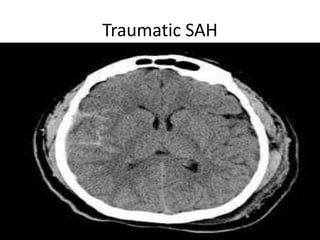

Traumatic SAH

Trauma • Soft tissueinjuries. • Skull fractures. • Extradural,subdural and subarachniod hemorrhage. • Contusions and diffuse axonal injury with associated cerebral odema.

Vascular Insults • SubarachniodHemorrhage. • Lobar and basal ganglia bleeds. • Ischemic strokes. • Venous infarcts. • Disections